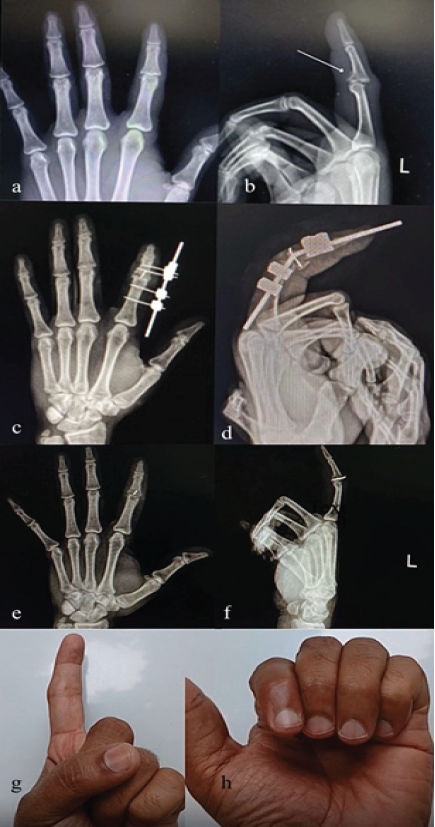

A 36-year-old male presented 7 days after trauma with a post-traumatic volar lip fracture of the middle phalanx of the left index finger. He was managed with a JESS external fixator. The patient was discharged with the external fixator in situ, which was removed after 4 weeks, and mobilization was started immediately thereafter. At follow-up, the patient achieved a ROM of 0–70° at the PIP joint (Fig. 5).

Figure 5: Pre Operative & Post Operative X-Rays, Post Jess Fixator Removal X-Rays & 6 Weeks Follow Up ROM Clinical Pictures (a) X-Ray Left Hand AP View, (b) X-Ray Left Index Finger Lateral View, (c) X-Ray Left Hand AP View showing Jess Fixator, (d) X-Ray Left Index Finger Lateral View, (e) Post Jess Fixator Removal X-Ray Left Hand AP View, (f) Post Jess Fixator Removal X-Ray Left Index Finger Lateral View, (g) Follow Up Image showing Finger Extension, (h) Follow Up Image showing Finger Flexion